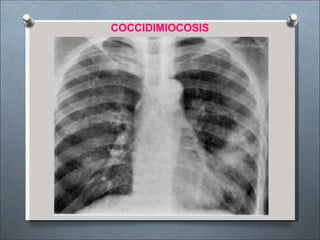

COCCIDIODOMICOSIS

•Enfermedad micótica altamente infecciosa

•Organismo causal: Coccidioides inmitis

•Vía de transmisión: Vía aérea - cutánea

contaminados,

mantienen el

•Fuente de infección: Suelos

Estiércol, roedores infectados

hongo en terreno.

Formas clínicas radiológicas:

•Enfermedad asintomática y tipo gripal.

•Tipo neumónico: Consolidación parenquimal de

lóbulos inferiores.

•Ensanchamiento linfático hiliar o mediastinico.

•Neumotórax.

•Lesiones nodulares con o sin cavitación.

•Lesiones miliares.